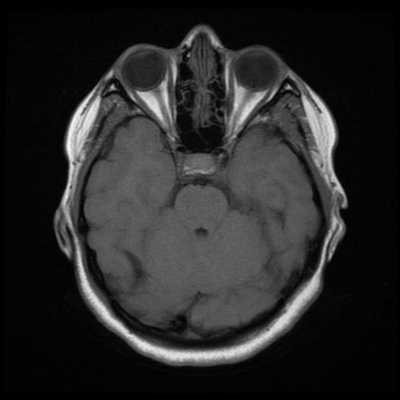

Исследование выполняется в нескольких режимах. Основные из них Т1 и Т2. Изображения, полученные в данных режимах, часто также называют Т1-взвешенными или Т2-взвешенными снимками. Изображения, показанные выше, сделаны в Т1-режиме.

Главное отличие этих режимов - в том, как на снимках отображается жидкость и воздух. В Т1 режиме ткани, содержащие большое количество воды, имеют более темную окраску, в то время как в Т2 режиме они яркие, светлые. Это легко понять, посмотрев на снимки выше - глазные яблоки визуализируются в виде светлых парных округлых образований с одной стороны яркие и светлые, с другой - темные. Следовательно, снимок справа сделан в Т1 режиме, снимок слева - в Т2. Также существует разница в том, как в этих режимах отображается серое вещество головного мозга. В Т2 режиме оно светлее, чем белое вещество.

Как же узнать, есть ли на снимках признаки болезни? Самое главное - запомнить, как выглядит головной мозг здорового человека. Врач, изучая снимки пациентов, постоянно сравнивает их с нормальными снимками, хранящимися у него в голове. Чтобы понять, как это происходит - посмотрите на снимки внизу:

Перед вами - два снимка, сделанных в одном режиме. Снимок снизу - норма. Какое заболевание, в таком случае, есть на верхнем снимке? Чтобы понять это, нужно сравнить эти изображения. Явно видно отличие - на верхнем снимке в правой части головного мозга есть новообразование. Разница еще заметнее, если сравнить левую и правую части того же снимка.

Отметим его красной окружностью. Визуально оно представляет собой узел, неоднородный по окраске и отличающийся от серого и белого вещества головного мозга. В таких случаях, чтобы точно определить границы опухоли и определить её тип исследование повторяют с контрастом. Введение контрастного препарата в кровь через локтевую вену приводит к накоплению контрастного вещества в тканях опухоли - нормальные здоровые ткани его практически не накапливают. И мы получаем следующую картину, показанную на рисунке справа. Яркая окраска опухоли соответствует накопленному контрасту - теперь можно не только сказать, где опухоль, но и примерно определить, что это доброкачественная опухоль, так как она имеет четкие границы (злокачественные опухоли прорастают окружающие ткани, из-за чего границы будут размытыми и не такими четкими).